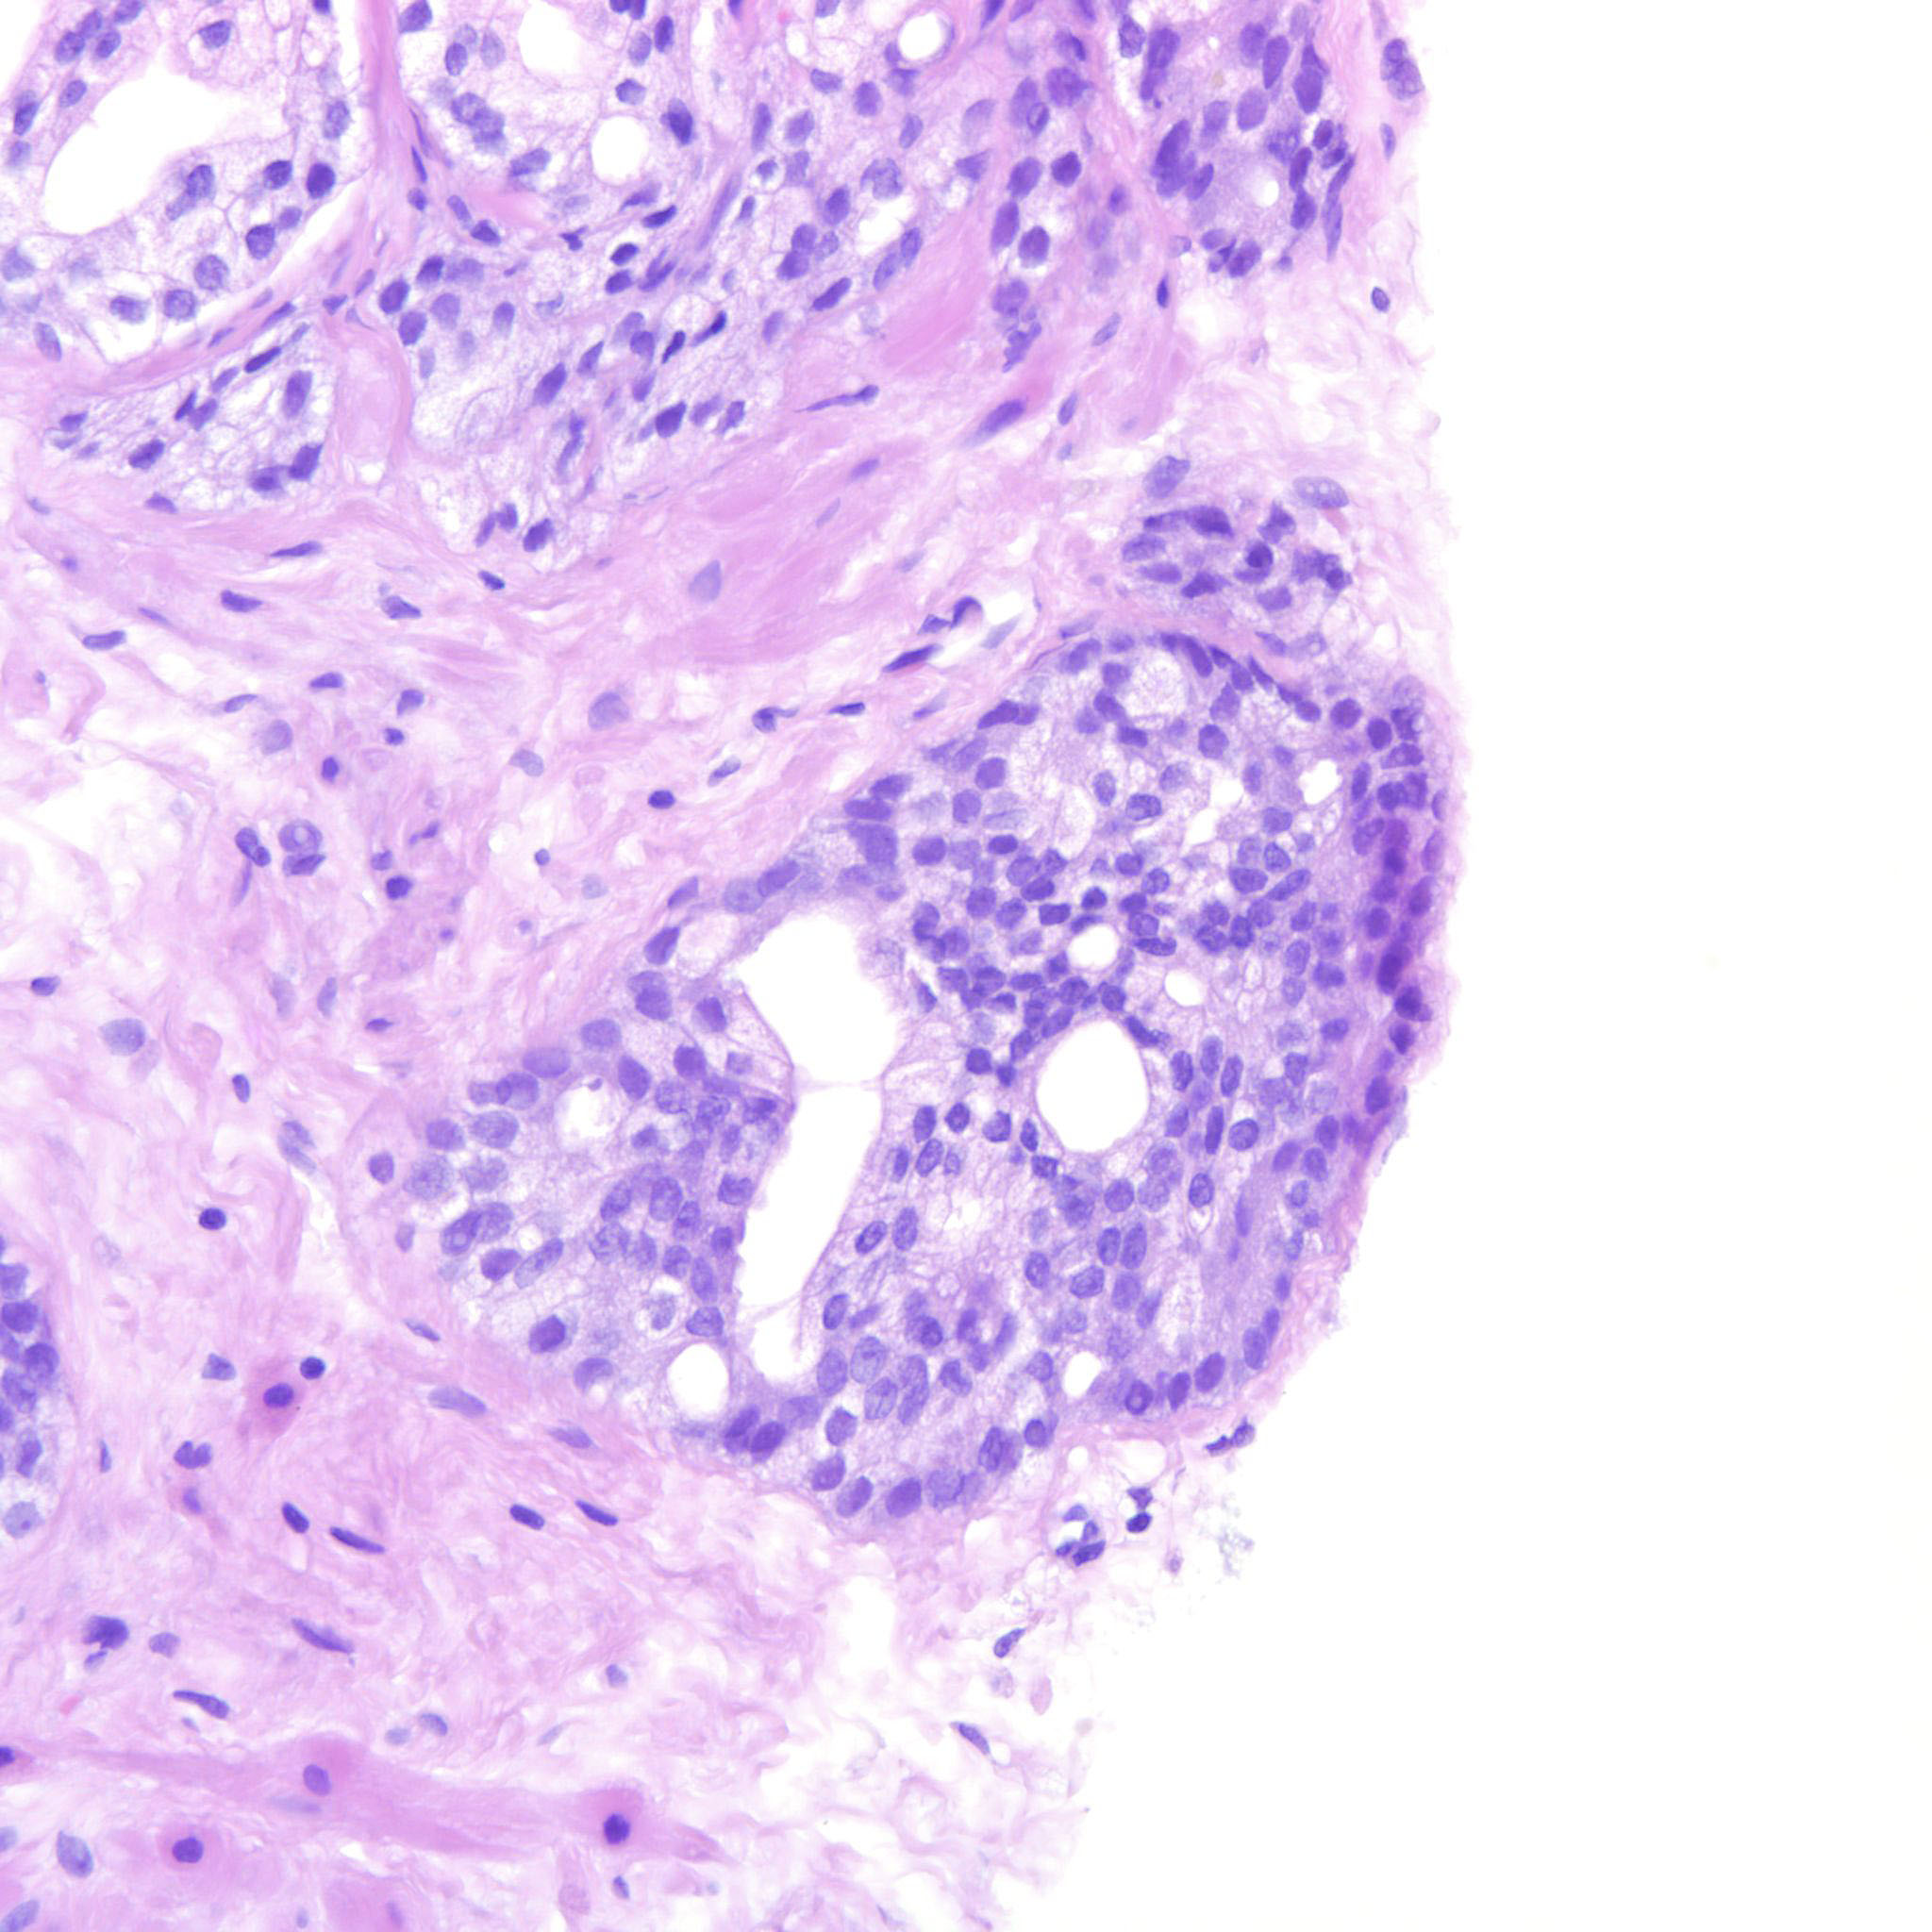

Prostate cancer grading

Case ID: 275